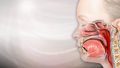

Sometimes, you can get a virus that makes you throw up or have diarrhea. Some people call this the "stomach flu." This is a misleading name because this virus is usually not the actual flu. The flu mostly affects your nose, throat, and lungs.

Normal lung anatomy - illustration

Normal lung anatomy

illustration